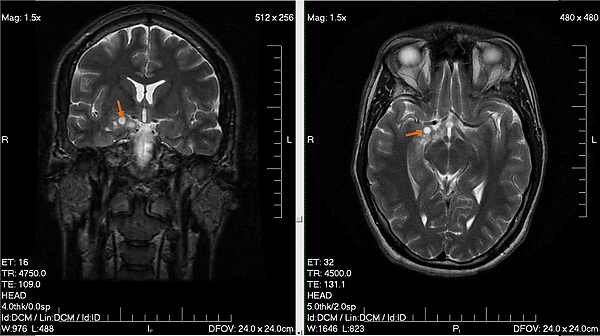

К обязательным методам обследования относятся определение активности сухожильных рефлексов, проверка тактильной и болевой чувствительности. Диагностические мероприятия могут быть расширены в зависимости от жалоб больного и с целью дифференциальной диагностики. Так, например, если больной отмечает нарушения координации, следует провести пальце-носовую пробу, проверить устойчивость в позе Ромберга. Если возникает подозрение на опухоль мозга, то больной направляется на компьютерную (КТ) или магнитно-резонансную томографию (МРТ). МРТ с контрастным усилением является «золотым стандартом» в диагностике опухолей головного мозга[5]. При обнаружении на томограмме объёмного образования решается вопрос о госпитализации больного в специализированный стационар.